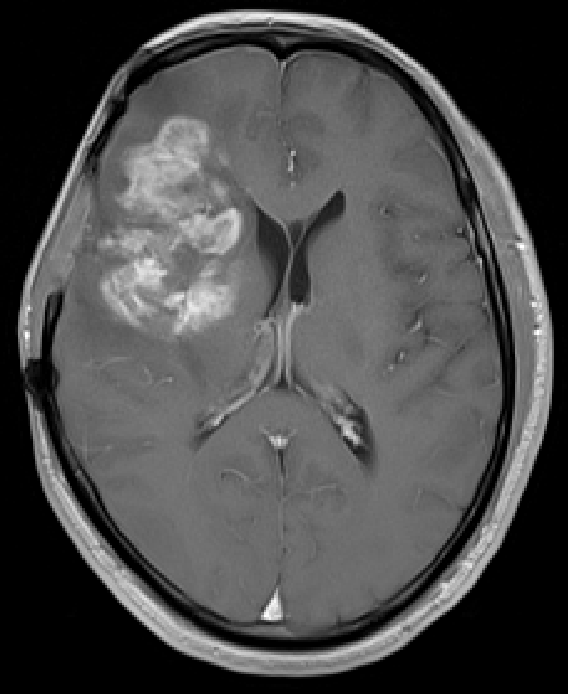

神經(jīng)外科團(tuán)隊(duì)的動作流暢而精準(zhǔn),每一步都顯得從容不迫。經(jīng)過數(shù)小時的激戰(zhàn),那些不請自來的“藝術(shù)創(chuàng)作”被徹底從王先生的腦子里清除。病理結(jié)果為(顱內(nèi)腫瘤組織)高級別膠質(zhì)瘤,考慮間變型少突膠質(zhì)細(xì)胞瘤,WHO III級。這不僅是一場醫(yī)學(xué)的勝利,更是科技與醫(yī)學(xué)完美結(jié)合的臨床治療實(shí)踐。

術(shù)前術(shù)后MRI增強(qiáng)